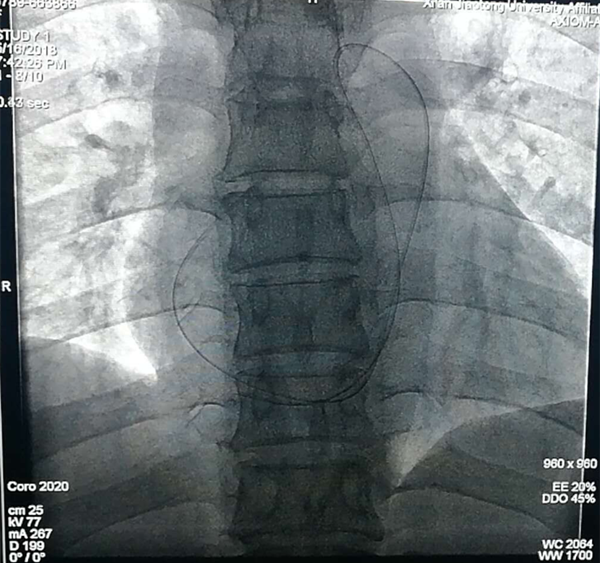

5月15日深夜,心内科导管室还是一片忙碌的景象,突然跑进来一个人,匆忙喊着急请心内科会诊,原来是妇产科的值班医生。听他讲述,当日晨收住一位妇科肿瘤患者,入院常规检查后给予输液治疗,这位患者和大多数患者一样,右上肢贵要静脉半年前于外院植入PICC导管,当护士去连接液体时,却发现异常,只见上臂透明敷贴下只露有一截残端,不见导管,询问患者感受,自诉无特殊不适。医护人员初步认定导管断入体内,为确认导管去向,急行床头拍片,最终确认断裂导管已随血流进入右心房。

正准备上台的郑强荪院长,韩振华主任,邓捷主任意识到情况严重性,收集患者主要资料,进行细致讨论。经外周植入中心静脉导管(PICC),作为化疗、反复输液等已被临床广泛应用,但如果护理不当会出现导管断裂现象,断裂的导管会随血流进入心腔,随时有可能发生栓塞、心律失常等,若抢救不及时可导致患者迅速死亡。意识到问题严重性,事不宜迟,与患者家属充分沟通后,最终决定天亮就为患者行心内介入术。

断裂入体内的导管